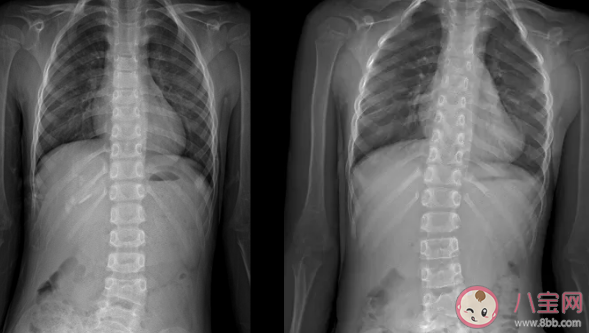

孩子處于身體快速發育的階段,長時間駝背,坐姿不正確很容易引發脊椎彎曲等問題,再要矯正的話就需要很長的時間,甚至是影響到體形,那么孩子脊柱側彎有哪些影響?下面帶來介紹。

02、外觀畸形

孩子脊柱側彎后,會出現兩個肩膀高度不一樣以及駝背等情況,導致身體外觀畸形。